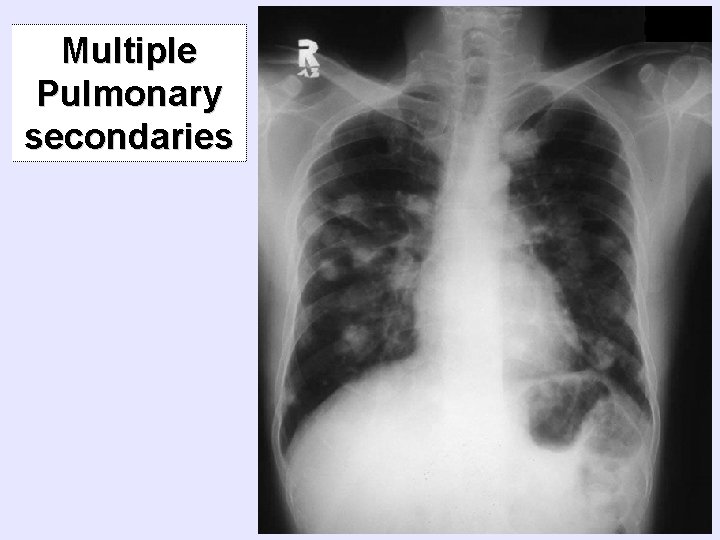

Multiple Pulmonary secondaries